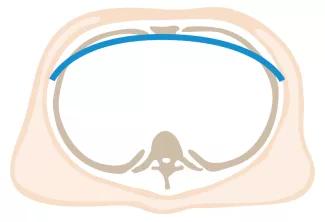

Repair with a metal pectus bar, called the Nuss Procedure, is achieved by bending a stainless bar to fit the chest wall. The bar is then inserted and secured through a small incision under each arm using the aid of a endoscope to monitor and avoid injury to the heart during insertion. The bar goes over the ribs and under the sternum, to push the sternum forward into the new position. The ends of the bar are secured to the chest wall. This procedure takes between 1–2 hours.